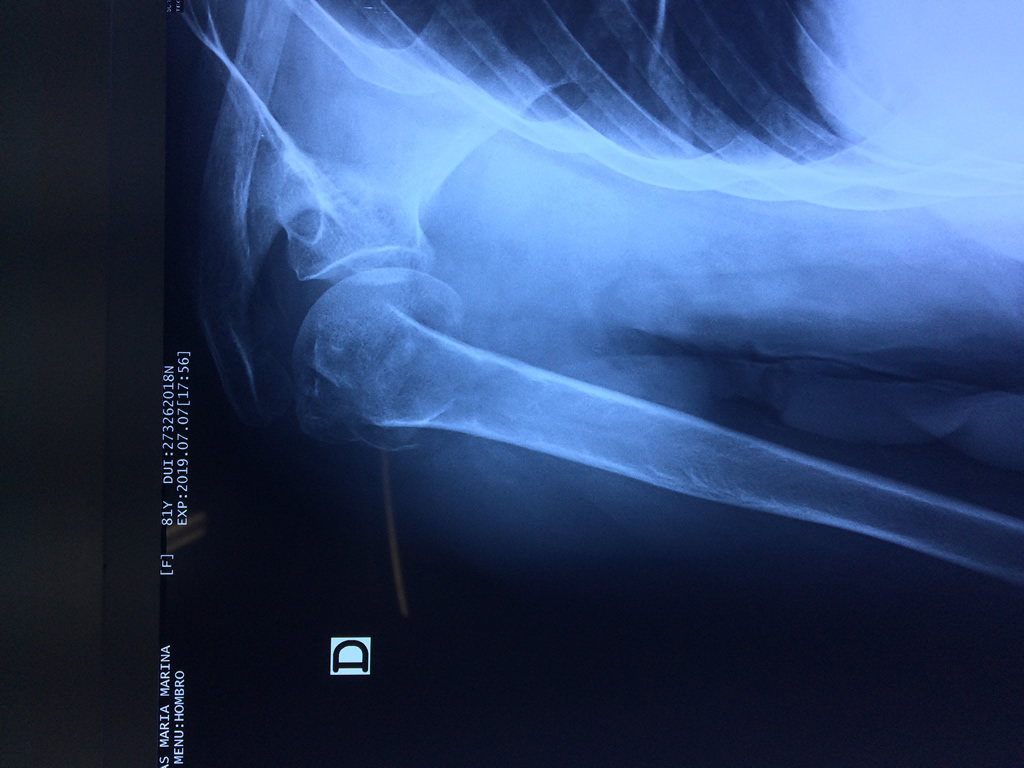

La principal articulación del hombro es la que une la cabeza del húmero con la escápula, recibe el nombre de articulación escapulohumeral y presenta dos superficies articulares, una de ellas corresponde a la cabeza del humero que tiene forma semiesférica y la otra es la cavidad glenoidea de la escápula, estas superficies están recubiertos por cartílago que permiten un movimiento suave e indoloro.

Varias estructuras transparentes en forma de saco llamadas bolsas serosas, permiten el deslizamiento suave de los diferentes componentes móviles. El hombro es la articulación con mayor amplitud de movimientos del cuerpo humano.